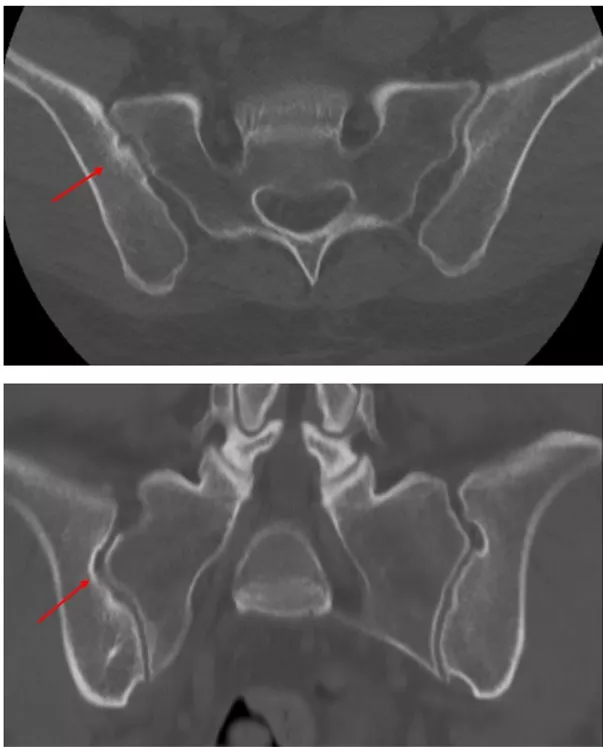

追加の病歴聴取で先行感染症歴や慢性的な下痢や血便なし。身体所見では全身に皮疹は認めず、爪の変形なし。血液検査ではリウマトイド因子陰性、抗CCP抗体陰性、抗核抗体陰性。HLA-B27は陰性。関節超音波検査で末梢関節に滑膜炎や付着部炎は認めず。単純X線で仙腸関節に明らかなびらん、骨硬化、狭小化なし(写真2)。仙腸関節CTでは右仙腸関節にびらん及び骨硬化を示唆する所見あり(写真3)。

写真2 仙腸関節Xp